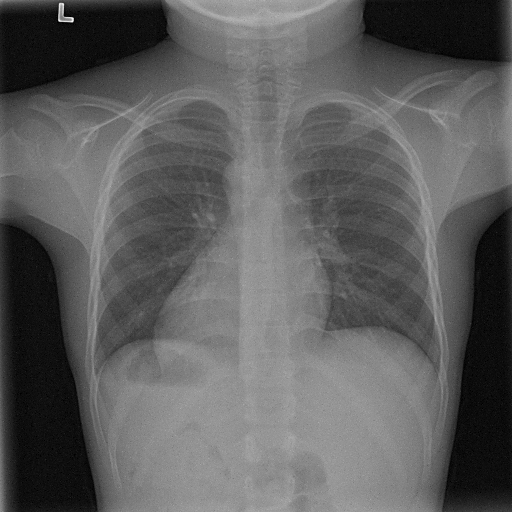

7.1 ϵitalic-ϵ\epsilon-LDP-processed CXR images

(a) Original

case 1

Figure 1: ϵitalic-ϵ\epsilon-LDP-processed CXR images (we applied the Laplace mechanism in the image domain).

In Fig. 1, we show four ϵitalic-ϵ\epsilon-LDP-processed CXR images of clinical cases obtained with the image domain LDP, which directly imposes the Laplace mechanism on the input image, with different privacy budgets together with the original images. Fig. 2 shows four ϵitalic-ϵ\epsilon-LDP-processed CXR images of clinical cases obtained with DP-GLOW and different privacy budgets together with the original images. In case 1 for DP-GLOW, there is decreased permeability in the bilateral hilar regions. Although this hilar opacity tends to be preserved with a larger privacy budget, the entire image is degraded when the privacy budget becomes 101HWsuperscript101𝐻𝑊10^{1}\cdot H\cdot W. A similar tendency is observed in the images of all the four cases for DP-GLOW; for example, in case 4 with ϵ=101HWitalic-ϵsuperscript101𝐻𝑊\epsilon=10^{1}\cdot H\cdot W, the lung opacity suggesting pneumonia in the right lower lung field is well preserved, while the entire image is degraded.